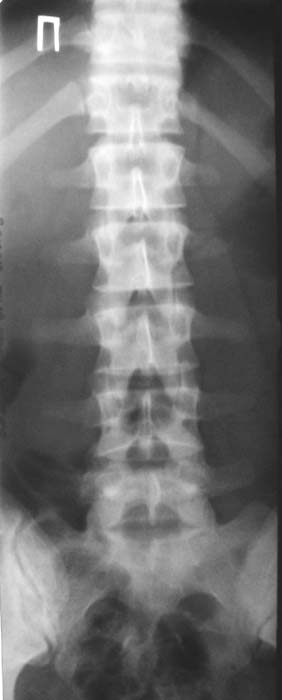

Уважаемые коллеги!Окажите, пожалуйста, консультативную помощь.Мужчина, 24 года. Туберкулез крестцово-подвздошного сочленения справа,

активная фаза. Болен в течение 6 месяцев. Проходил курсы НПВС - без эффекта.Жалобы на постоянные боли в поясничной области. Местно: крестцовая область припухшая, кожа не изменена, при пальпации боль, осевая нагрузка - боль, хромота на правую ногу.Общие анализы - без особенностей.МРТ 09.11.03. - патологических изменений в поясничном отделе не выявлено.Описание рентгенолога: остеосклероз, нечеткость контуров, участки деструкции в правом крестцово-подвздошном сочленении.Положительный анализ на антитела к микобактериям (IgM+E) от 16.10.03.Вопросы: уточнение диагноза, определение тактики лечения.С уважением,А.В.ВладзимирскийДонецкий НИИ травматологии и ортопедииДонецк, Украина

"Представленные рентгенограмы не убедительны с точки зрения наличия деструктивного процесса в крестцово-подвздошном сочленении. Необходимо выполнить компьютерную томографию таза с обязательным захватом крестцово-подвздошных сочленений. Желательно также знать рентгенологическую картину легких."